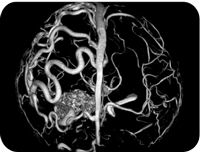

CT Scan

The computerized tomography, CT, produces a detailed image of the internal structure of the body by combining results from different x-rays. The CT scan provides the image of the internal structure of the body in 2- dimensional figure, but the images produced can be used to create 3-dimensional figures. We do provide denta scan & all special C.T. Angiography through the fastest scanner Seimens Bright speed 16 slice C.T. Machine Visit Lifecare Scan & Research for next gen CT Scan in Durg & Bhilai at affordable cost.